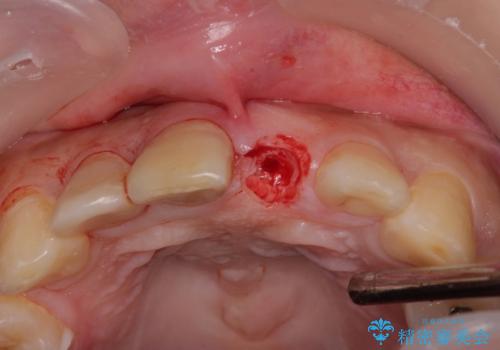

- 転倒により前歯を失ったところにインプラント治療を受けたいとのことで来院された患者様です。

転倒を機に矯正治療を行ったようで、歯列が整い、インプラントのスペースができたとのことで受診をされました。

骨量は十分にあったため、インプラント埋入後速やかに仮歯を装着して、歯肉治癒後にオールセラミッククラウンによる補綴治療を行うこととしました。